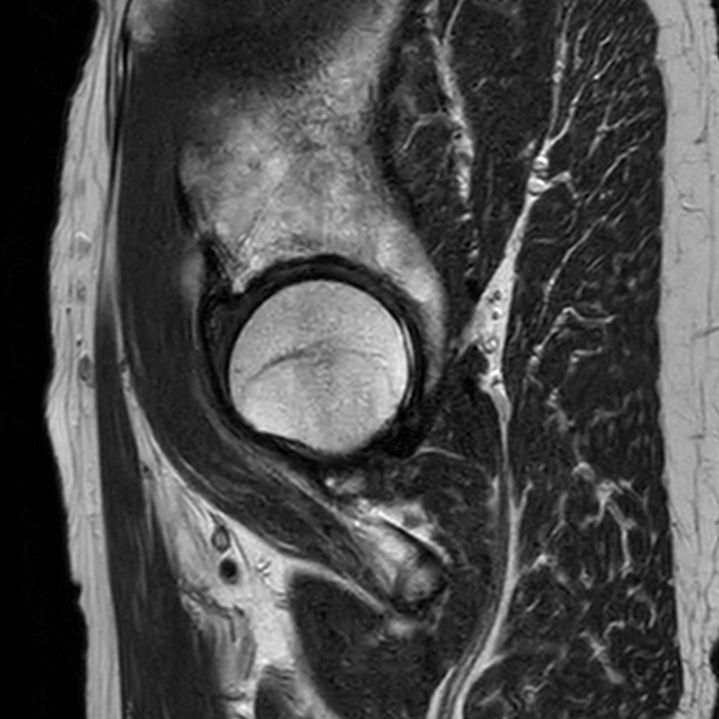

Sagittal T2w TSESmartSpeed

-